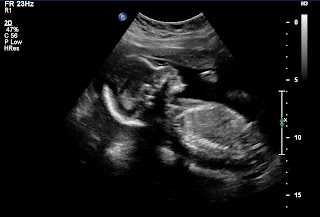

On the Wednesday of my last week at DFAS, several dear co-workers and friends put together a Farewell Party/Baby Shower and invited co-workers from every department where I've worked. It was so great to see everyone one last time before I come back in November to shamelessly parade my sweet baby through the office. Here are all the pictures I got from Becky...instead of getting a group picture we seemed to just take individual shots, so you're going to see a lot of my green dress...